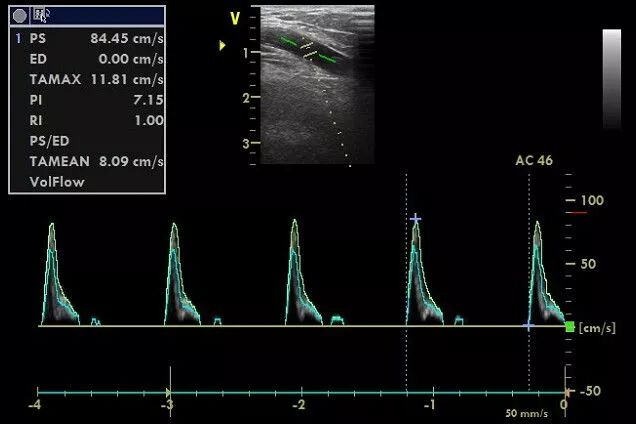

下图中的取样容积基本包括整个血管腔,频谱较宽,涵盖了贴壁的低速血流,说计算得平均速度较为准确。

什么是超声容积探头血流量测定 |取样容积和角度θ_https://www.jmylbn.com_新闻资讯_第5张